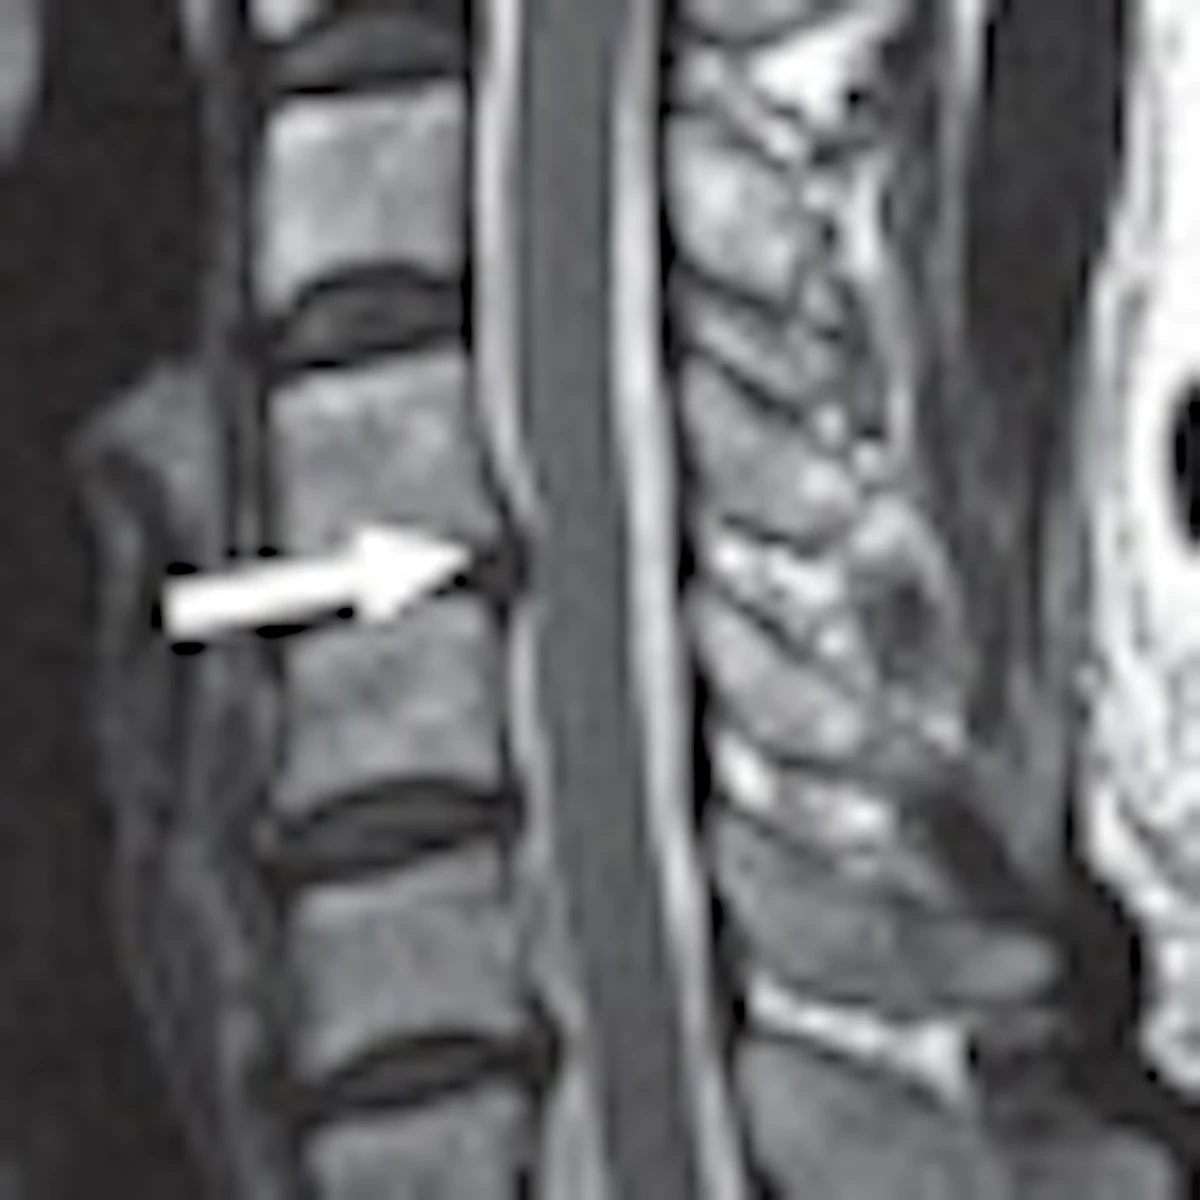

T2 W Sagittal MR images of the cervical spine showing Kang’s grade 0 ...

Figure 1 from Radiologic Assessment of Cervical Canal Stenosis Using ...

Figure 2—62 from New MRI grading system for the cervical canal stenosis ...

Figure 4—61 from New MRI grading system for the cervical canal stenosis ...